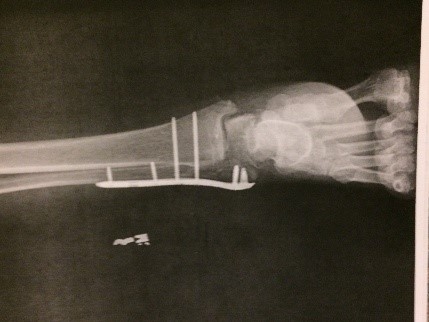

Attached is a picture of my foot about 30 days after a team of surgeons re-attached it following a horrific car accident; I had just gotten my cast removed.

I was airlifted to the nearest Trauma Hospital – where a group of remarkable surgeons spent hours re-attaching my foot to my ankle.  In addition, they fixed my fibula and tibia bones which were broken (and needed a plate screwed to them), and inserted a rod in my broken femur bone all the way from my hip to my knee.  Finally they put a plate and screws in the humerus bone in my right arm; three fractured ribs were left to heal themselves.

2. About 4 weeks later (second week of September) I started physical therapy at the local hospital.  My insurance company had approved 8 weeks of therapy three times a week. I was nicknamed the Bionic Woman because of all the hardware I had implanted in my body.